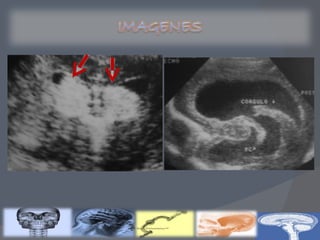

Recién nacidos con factores de riesgo : Prematuros Síntomas neurológicos Condiciones de riesgo  USG TRANSFONTANELAR (Primeros 5 días)

Clasificación de Volpe por ultrasonido transfontanelar Clasificación de Papile por tomografía axial computarizada Gravedad de la HIV Descripción GRADO I Hemorragia de la matriz germinal mínima(<10% del área ventricular) GRADO  II Hemorragia del área ventricular de 10 a 50% GRADO  III Hemorragia del área ventricular >50% Hemorragia intracerebral u otra lesión parenquimatosa Gravedad de la HIV Descripción % de HIV GRADO  I Hemorragia de la matriz germinal 40 GRADO II Hemorragia con tamaño normal de los ventrículos 30 GRADO III Hemorragia  con dilatación ventricular 20 GRADO IV Hemorragia ventricular, más parenquimatosa 10

GRADO 1 La hemorragia está localizada únicamente en la matriz germinal subependimaria GRADO 2 Contenido de sangre intraventricular que ocupa menos del 50% del área ventricular en una proyección parasagital GRADO 3 La sangre ocupa un área mayor del 50%, distendiendo el ventrículo Cuando existe una hemorragia intraventricular masiva que sobredistiende de forma muy importante los ventrículos laterales y, en general, todo el sistema ventricular está ocupado:tercer y cuarto ventrículos y espacio subaracnoideo de fosa posterior (cisterna magna)

Recién nacidos confactores de riesgo : Prematuros Síntomas neurológicos Condiciones de riesgo USG TRANSFONTANELAR (Primeros 5 días)

Clasificación de Volpepor ultrasonido transfontanelar Clasificación de Papile por tomografía axial computarizada Gravedad de la HIV Descripción GRADO I Hemorragia de la matriz germinal mínima(<10% del área ventricular) GRADO II Hemorragia del área ventricular de 10 a 50% GRADO III Hemorragia del área ventricular >50% Hemorragia intracerebral u otra lesión parenquimatosa Gravedad de la HIV Descripción % de HIV GRADO I Hemorragia de la matriz germinal 40 GRADO II Hemorragia con tamaño normal de los ventrículos 30 GRADO III Hemorragia con dilatación ventricular 20 GRADO IV Hemorragia ventricular, más parenquimatosa 10

GRADO 1 Lahemorragia está localizada únicamente en la matriz germinal subependimaria GRADO 2 Contenido de sangre intraventricular que ocupa menos del 50% del área ventricular en una proyección parasagital GRADO 3 La sangre ocupa un área mayor del 50%, distendiendo el ventrículo Cuando existe una hemorragia intraventricular masiva que sobredistiende de forma muy importante los ventrículos laterales y, en general, todo el sistema ventricular está ocupado:tercer y cuarto ventrículos y espacio subaracnoideo de fosa posterior (cisterna magna)